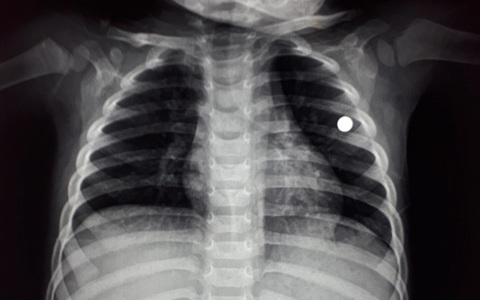

TTO - Chiều 20-2, Bệnh viện Nhi Thanh Hóa cho biết các bác sĩ vừa phẫu thuật, cấp cứu cháu L.V.V., 4 tuổi, bị đạn bi bằng chì găm vào ngực trái, cạnh tim.